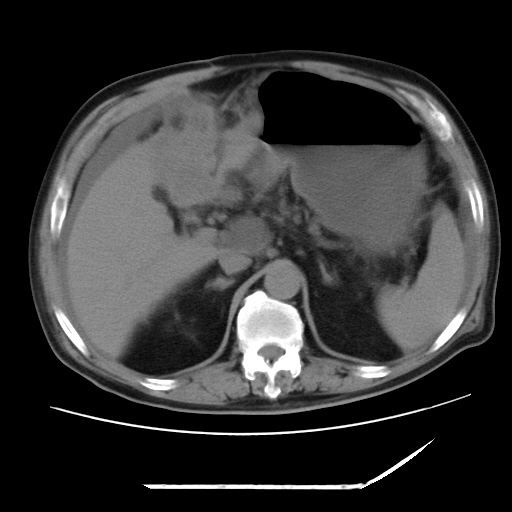

以下是引用zxl51642在2009-8-12 18:55:00的发言:[br]1、肠系膜脂肪浑浊,密度增高,腹水,支持腹膜炎诊断;2、右肾盂及输尿管中段结石,左输尿管起始段结石;3、胆囊切除术后改变?4、双侧胸膜腔少量积液;5、胰腺体积不大,勾勒清楚,肾前筋膜无增厚,不支持胰腺炎,请结合血尿淀粉酶及临床。